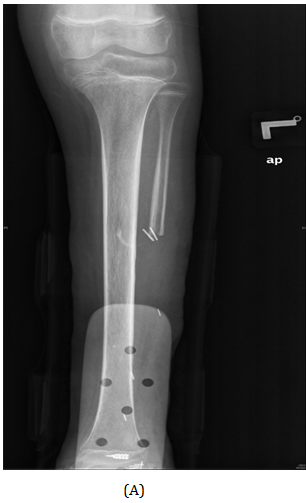

A girl, 11yearsold Saudi presented to us with progressive swelling of the left lower limb, localized above the left ankle with complaints of pain and limping gait. She had visited many clinics for her pain and swelling with no relief to her symptoms. The patient was examined clinically and there was a swelling in the lateral aspect of the distal leg tender firm too hard with intact skin over it, 4x3 cm, no other systemic clinical finding of note. X-ray of the left leg (Figure 1) showed aggressive lytic lesion of the distal fibula. Thence patient was investigated with basic lab works plus systemic and local staging for further diagnosis. She was admitted under us in pediatric surgical ward for open biopsy of the distal fibular lesion and CT of the lower limb (Figure 2) showed destructive bone lesion involving the distal end of the fibula associated with extensive destruction and aggressive periosteal reaction associated with large soft tissue mass 4.5 x 5 cm in maximum axial dimension. Also, MRI of the lower limb (Figure 3) showed there is a large destructive bone lesion involving the distal diaphysis of the left fibula. This lesion does not cross the growth plate. It is associated with aggressive periosteal reaction along with a large soft tissue mass that appears of high signal intensity in T2 and intermediate to low signal intensity in T1 sequences. This was followed by technetium-99m MDP scintigraphy (Figure 4), it showed an increased tracer uptake in the distal left fibula, extending to the left ankle and the left foot. Excisional biopsy was taken from the proximal and distal margin of the lesion in the left fibula which confirmed Ewing's Sarcoma. According to the histopathology department, they reported that there is no evidence of residual tumor i.e free resection margins. (Figure 5) The patient was referred from us to pediatric oncology clinic for further evaluation. She was electively admitted to the hospital for staging and central line insertion to start chemotherapy. She treated as per Ewing sarcoma protocol in our hospital. Patient was put on neoadjuvant chemotherapy which included vincristine, cyclophosphamide, doxorubicin and etoposide, and if osfamide 3 times weekly. After 6 months of chemotherapy, we recommend to her family to do a surgery. We did a wide surgical resection of the tumor in the left leg. Subcutaneous tissue was dissected and isolation of superficial peroneal nerve was done. Dissection of lateral compartment of the left leg up to 16cm proximal to the lateral malleolus and distally, until the distal physis (Figure 6). The tendons of the peroneus longus, peroneus brevis, and flexor halluces longus were sacrificed and the ruminants were used to reconstruct for the lateral aspect of the left ankle using suture anchors (Figure 7). K-wires were used to do temporary arthrodesis (Figure 8). The surgical wound was closed in layers. VAC dressing was also applied as standard care management in Oncology cases at KFMC and backs lab was applied (Figure 9). The last MRI done for the patient showed there is altered signal intensity of the soft tissue with post-contrast enhancement. However, the dimensions of this area of altered signal intensity are decreased as compared to previous MRI. There is no evidence of soft tissue mass lesion (Figure 10). According to the last patient's follow up after six months post-operation it shows no Valgus deviation, normal ankle motion, mobilizing full weight bearing with splint assistant during physical examination (Figure 11). Also, X-rays and MRI finding shows no residual mass lesion or local recurrence.

Figure 1 AP view of plain X-ray of the left leg showed ill-defined lesion involved distal end of the fibula (diaphysis) with cortical destruction and soft tissues swelling.

Figure 6 Interoperation images. Tumor in the distal end (A). Remnant of Prenous Longus Tendone (B). Isolation of the Superficial Peroneal Nerve (C). Resection of distal Fibula Tumor (D) Tumor resected with reservation of neurovascular pedicle (E). VAC dressing (F). AP view of plain X-ray of the left leg showed dissection of lateral compartment of the left leg during resection of the tumor (G).

Figure 7 Anteroposterior ( A ) and lateral views ( B ) of plain X-ray of the left leg showed the tendons of the peroneus longus, peroneus brevis ,and flexor hallucis longus were cut and they were used to reconstruct for the lateral aspect of the left ankle using suture anchors.